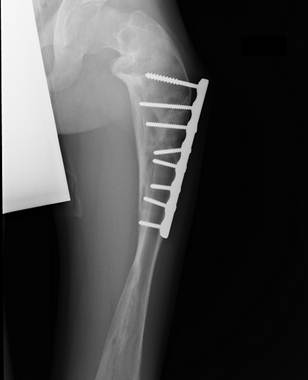

Сросшийся

перелом бедра у мальчика 13 лет с несовершенным остеогенезом, остеосинтез простой пластиной со множеством

винтов. Видна типичная деформация

бедренной кости по типу «галифе», следы

неоднократных переломов в прошлом.

Применение операции Богданова в

возрасте 5- 6 лет позволило бы избежать этих негативных явлений и предотвратить

переломы.